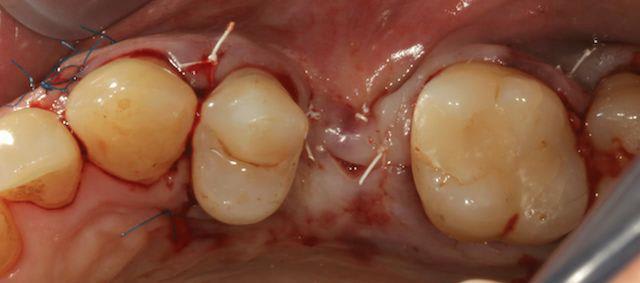

Le top c'était le gore-tex, mais il n'est plus produit donc je me suis rabattu sur le cytoplast qu'on trouve en france chez dentalforce, et pour les tissus fins, les décharges en particulier du prolène en 6,0. Je te joins qq photos.

Ton biomat c'est quoi?

Sinon sur le fait d'utiliser des membranes qui se résorbent à long terme c'est pas forcement une bonne idée.

Et je suis entierement d'accord avec toi sur le fait de pinser la membrane, par contre peut être que tu n'as pas besoin de mettre des vis, mais bon ça peut pas faire de mal ;)